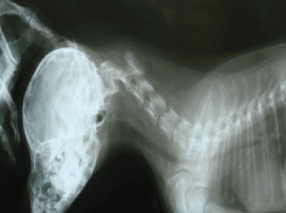

Вряд ли в наше время найдется человек, который хотя бы в общих чертах не знает, что такое рентгенография. Существует огромное количество симптомов, при которых врач говорит: «Давайте-ка сделаем рентген». Но до сих пор многие владельцы животных недооценивают ценность этого метода диагностики, или ж...